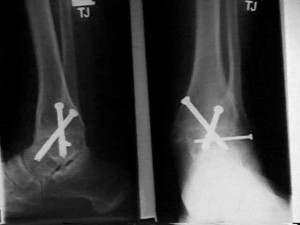

Артодез на этом суставе могут проводить как под общей, так и под спинальной анестезией. Для сращивания могут использовать специальные шурупы, винты, пластины, стержни, костные трансплантаты и другие медицинские приспособления для фиксации.

Во время операции пораженный сустав удаляется и обеспечивается сращивание двух костей, или создается искусственный костный анкилоз.

В процессе хрящевые поверхности таранной и большеберцовой костей удаляются, они сопоставляются и фиксируются. Человек перестает чувствовать боль, но также происходит компенсирование объема движений и нарушаются двигательные функции.